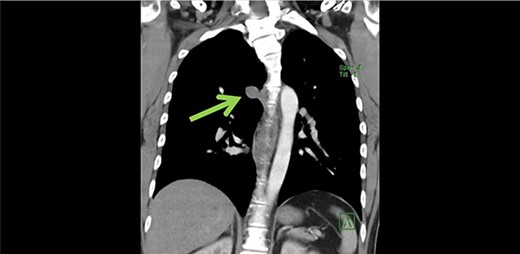

Subsequently cardiac magnetic resonance imaging (MRI) established the presence of a well-defined lobulated hyperintense HASTE lesion at the right paraspinal lesion, posterior to the carina at T4/T5 level, measuring 1.2 cm × 3.1 cm × 1.5 cm. (Figs 1 and 2) There was no regional wall motion abnormality, ventricular strain, valvular incompetency or pericardial effusion. Further contrast enhanced computed tomography (CECT) thorax with complementary MRI thoracic spine confirmed the location of the lesion, and it appeared to be in continuity with the adjacent AV. On the complementary MRI, the lesion showed isointense signal on T1, hyperintense signal on T2 and T1RM. On CINE sequence, there was continuous blood flow within this lesion to the AV. A diagnosis of AVA was made.